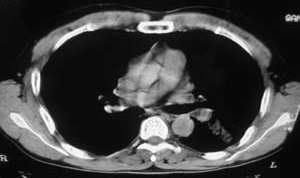

以下是引用ysxyy在2006-3-4 20:19:00的发言:[br]首先考虑炎症,tb暂不考虑;[br]理由:1、病变范围局限在左上肺尖后段,界限较清;[br]2、病史:青壮年34岁,以咳嗽、发热就诊,急性起病;[br]3、

以下是引用lkc8963在2006-3-4 21:27:00的发言:[br][quote]以下是引用ysxyy在2006-3-4 20:19:00的发言:[br]首先考虑炎症,tb暂不考虑;[br]理由:1、病变范围局限在左上肺尖后段,界限较清;[br]2、病史:青壮年34岁,以咳嗽、发热就诊,急性起病;[br]3、